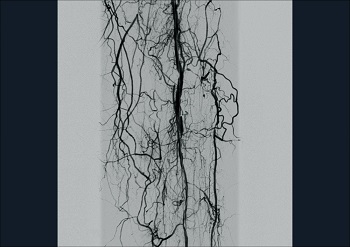

— Субстракционная ангиография

Ziehm Vision RFD - уникальный мобильный рентгеновский аппарат с возможностью многостороннего клинического применения. Плоскопанельный детектор аппарата дает отличные высокоточные изображения, обеспечивая прекрасную визуализацию для инвазивной радиологии, нейрохирургии, сосудистой хирургии, кардиологии и при инвазивных процедурах, таких как аневризма абдоминальной аорты или ЧТКА, и находит также применение в гибридных областях,

как например, при имплантации аортального сердечного клапана.

Компания Ziehm Imaging впервые предоставила возможность использовать все достоинства плоскопанельных детекторов в мобильных установках. Благодаря плоскому детектору 30 х 30 см область видимого поля увеличилась в 2.5 раза по сравнению с обычным усилителем изображения 23 см. Отсутствие S-образной дисторсии, широкий динамический диапазон и превосходное отображение всех анатомических деталей делает этот аппарат идеальным выбором для широкого спектра клинических процедур.

Ziehm Vision RFD - уникальный мобильный рентген с плокопанельным детектором для многостороннего клинического применения. Аппарат дает отличные высокоточные результаты в инвазивной радиологии, нейрохирургии, сосудистой хирургии, кардиологии и при инвазивных процедурах, таких как аневризма абдоминальной аорты или ЧТКА, и находит также применение в гибридных областях, как например, при имплантации аортального сердечного клапана. Специальный программный пакет SmartVascular позволяет выполнять цифровую субтракционную ангиографию, в том числе с возможностью использования CO2 как контрастного вещества. Возможность установки дополнительных потолочных мониторов и внешнего интерфейса управления, а так же расширенное орбитальное вращение штатива делают Ziehm Vision RFD незаменимым аппаратом для многофункциональных операционных.

• Программный пакет для сосудистой хирургии: DSA, MSA, RSA и CО2